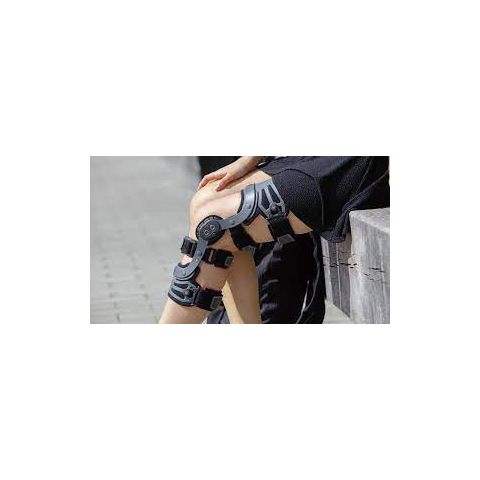

1 kép

1 kép Otto Genu Immobil Vario térdortézis

31 290 Ft-tól

Otto Genu Immobil Vario térdortézis Otto Genu Immobil Vario térdortézis A Genu Immobil Vario stabil,állítható mozgástartományú térdortézis szabályozható mozgásterjedelmű oldalsínnel. Képes a műtét utáni nyugalomba helyezésre éppen úgy, mint a korai mo